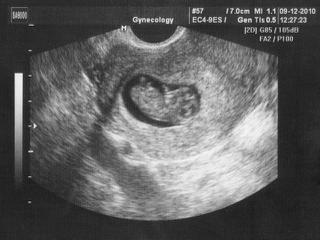

@kuratkol chápu,že jsi rozrušená... chci tě uklidnit.... taky jsem měla T21 poměr 1:290 .. a Maruška je zdravá. Jestli tě pošlou na plodovku,tak to záleží na tobě... já šla,chtěla jsem mít 100% jistotu, protože vím, že nejsem natolik silný člověk, abych se pak starala o postižené dítě... prostě jsem na tu plodovku šla (i když jsem věděla o pravděpodobnosti potratu po zákroku - ale je to jen 1%)... nemáš to lehký holka ☹ ale to bude dobrý,musíš tomu věřit a netrápit se.... prožila jsem si to a vím,že jsem brečela tři dny v kuse zbytečně... ale ty obavy tam samozřejmě jsou...

@kuratkol jak píše kualalik, je jasný, že jsi rozrušená, to by byla každá, ale jestli chceš mít 100% jistotu, že je mimísek v pořádku tak bych asi riskla tu plodovku. Moc ti držím palečky aby bylo naprosto všechno v pořádku. Drž se!!!!